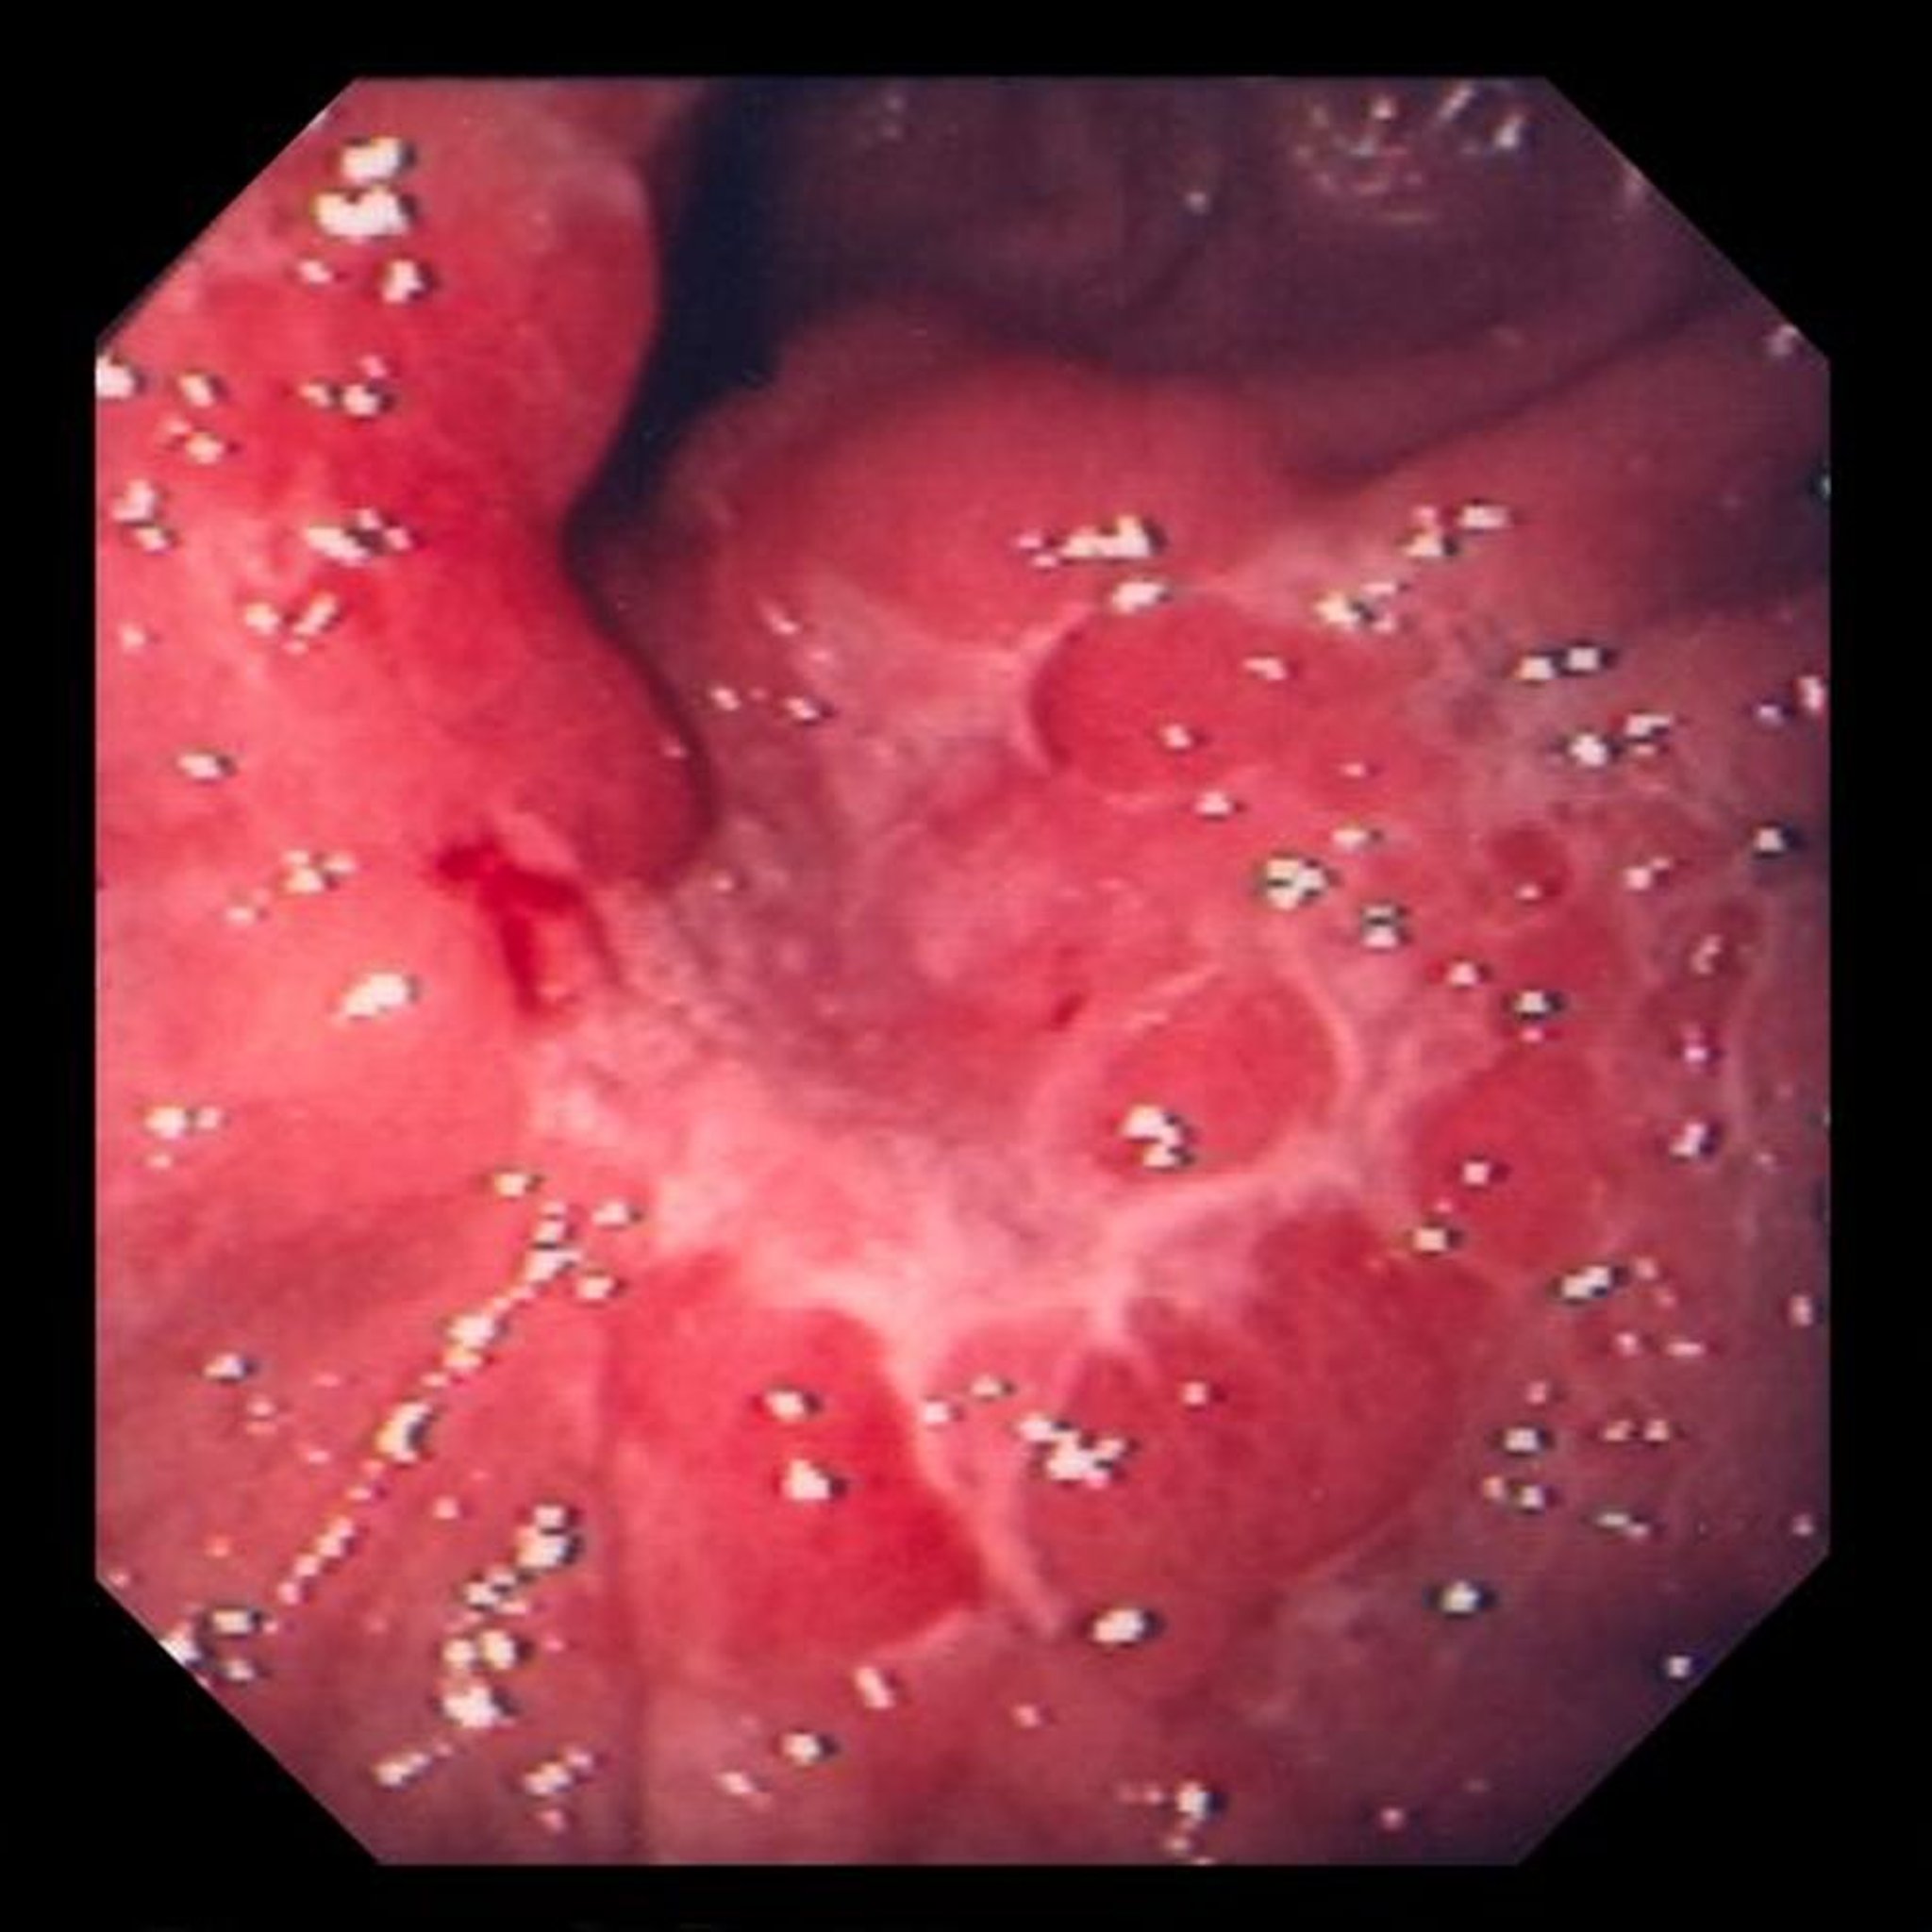

Dieses Bild zeigt ein Ulkus in den ödematösen Schleimhautfalten, das sich bei der Biopsie als schlecht differenziertes Adenokarzinom (Siegelringzelltyp) herausstellte.

Image provided by David M. Martin, MD.